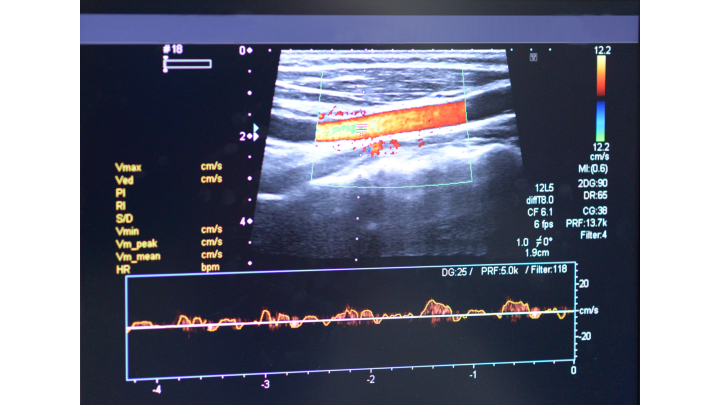

While 2D ultrasound imaging can provide images in real time even if the target moves, 3D ultrasound imaging is much more sensitive to changes in movement. Repositioning limbs, for example, may be necessary to make different parts of a limb available to the ultrasound probe in order to image an entire artery. The angle of the 2D image changes from its original position, making it difficult to stitch the images together into a 3D representation.

Robotic ultrasound systems (RUSS) produce high quality images by precisely controlling the contact force and orientation of the ultrasound probe. Combining robot arms with depth cameras to determine optimal probe position increases the accuracy of the scan. This is still not effective for 3D imaging because this system also cannot account for movement of the scan target.

The new system developed by the researchers, as described in the paper titled “Motion-Aware Robotic 3D Ultrasound” (bit.ly/VSD-MTN3D), combines RUSS with depth cameras to make 3D imaging with ultrasound possible. The system uses a LBR iiwa 14 R820 robot arm from Kuka (Augsburg, Germany; www.kuka.com/en-us), a Cicada LX ultrasound machine from Cephasonics Ultrasound (Santa Clara, CA, USA; www.cephasonics.com), and an Azure Kinect 3D camera from Microsoft (Redmond, WA, USA; www.microsoft.com/en-us).